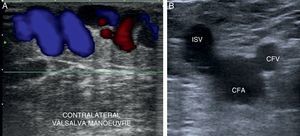

Valsalva manoeuver: increasing thoraco-abdominal pressure2,10,11,18 (Fig. 8A).

To confirm the presence of reflux we will use these manoeuvers:

- •

We will begin the study at the level of the sapheno-femoral junction in B-mode (Mickey Mouse sign) (Fig. 8B).